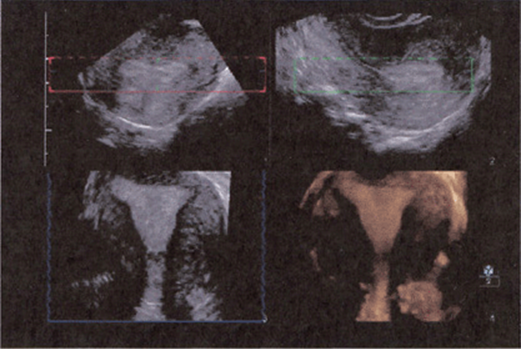

Automated 3D transducer probes contain an array of transducer elements that are swept in a selectable arc through an area of interest. The images are displayed in a multiplanar format with the long-axis, short-axis, and coronal planes, as well as the volumetric image. The multiplanar images are usually displayed with the long-axis view on the top left, followed by the short-axis images obtained at 90° or orthogonal to the long axis displayed in top right, followed by the coronal image scan plane (Fig. 8–3, bottom left). The combined volume is shown, within which (Fig. 8–3 bottom right) the scan plane can be maneuvered.

FIGURE 8–3. Multiplanar imaging format. (Courtesy of Philips Healthcare.): Top left: long-axis plane; Top right: short-axis plane; Bottom left: coronal plane; Bottom right: 3D volume.